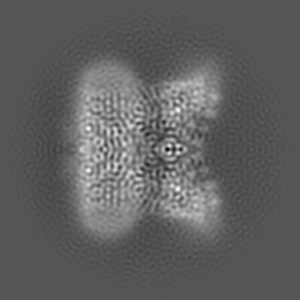

Inactivated-state cryo-EM structure of human TRPV3 in presence of tetrahydrocannabivarin (THCV) in cNW30 nanodiscs

Single-particle3.63 Å

Sample: full-length human TRPV3 in complex with THCV